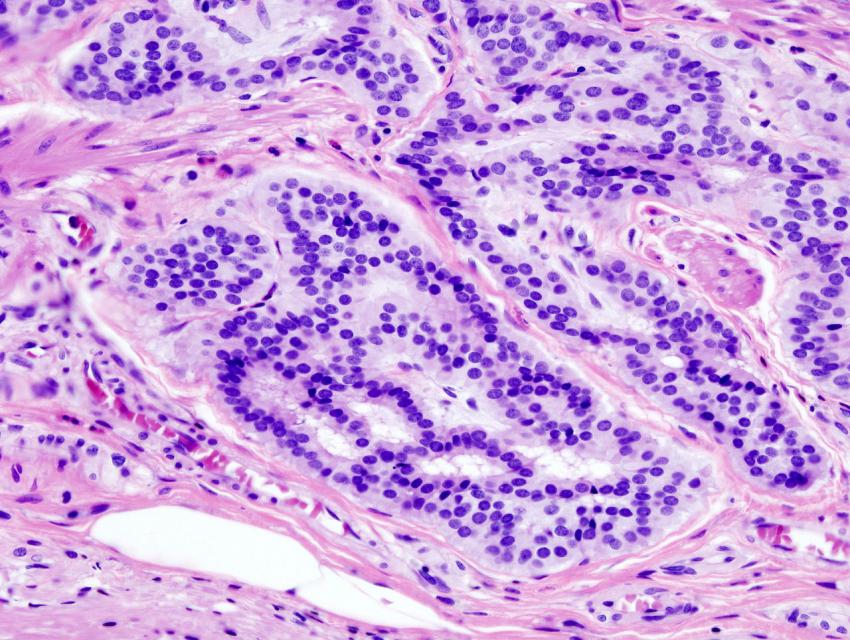

«Золотым стандартом» диагностики предраковых заболеваний является эндоскопическое обследование – колоноскопия. Процедура позволяет вовремя обнаружить опухоль, сразу же взять биопсию и даже провести некоторые лечебные манипуляции.